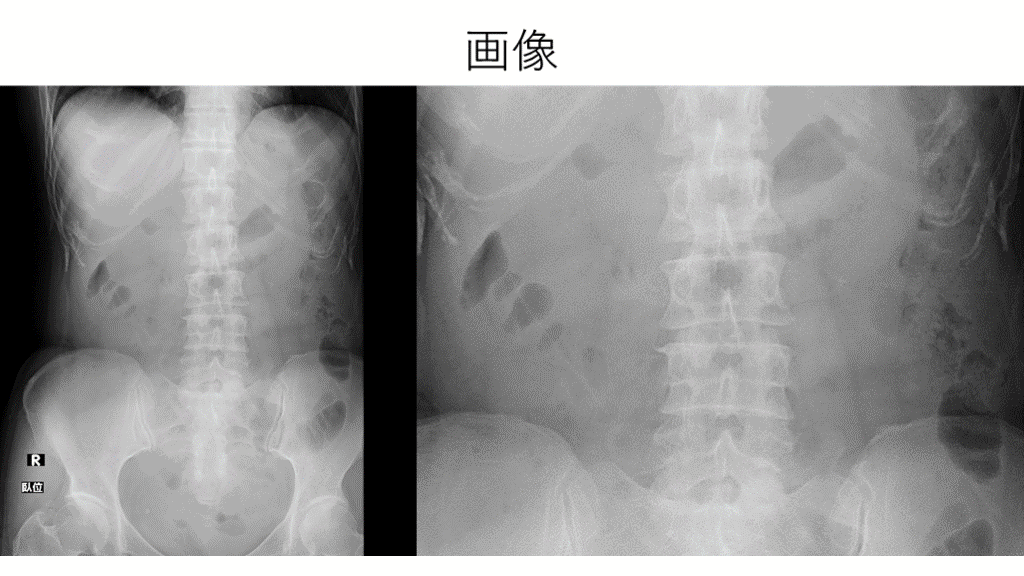

画像

画像 ? 右Psoas line 陰性

Psoas line (腸腰筋陰影) 腸腰筋の外側辺縁は後腹膜の脂肪織と接している。 同部に腫瘍や炎症が生じると、腸腰筋の陰影が欠損。(陰性) シルエットサインの一種。 健常人でも20%では認められない。(特に肥満体型) 左右両側で陰性ならOKだが、片方だけ陰性なら異常を疑う。